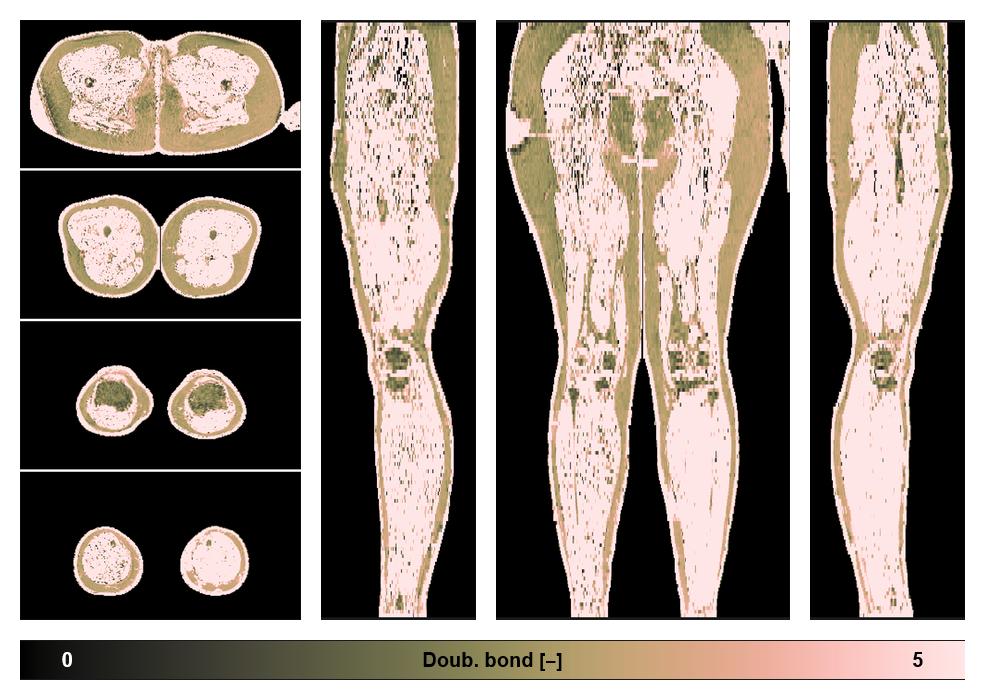

• Number of double bonds in subcutanious fat

Number of double bonds in subcutanious fat.